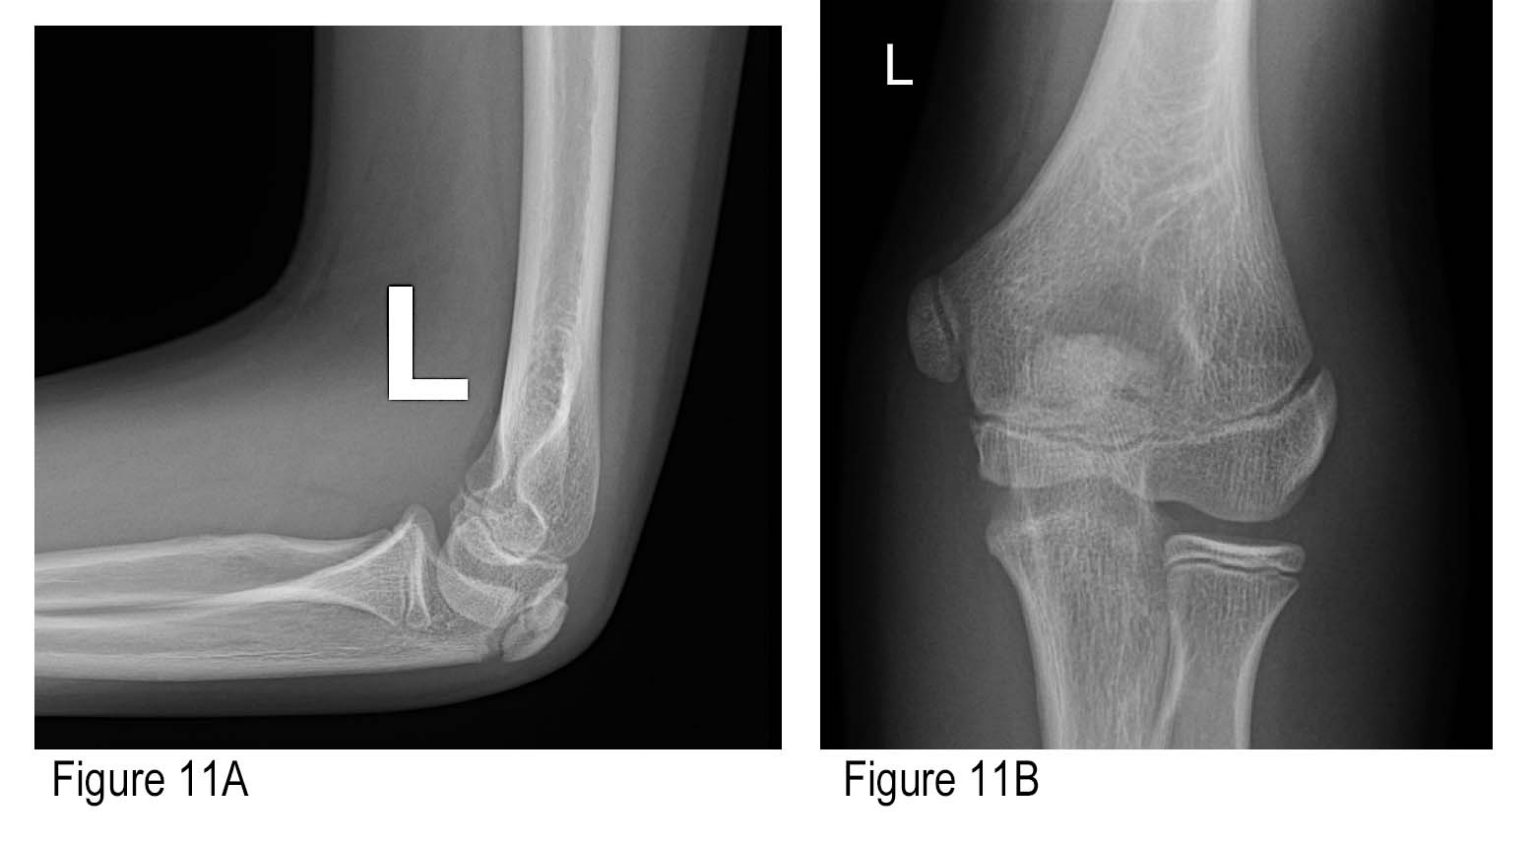

In children, many fractures can be treated with a cast, but some more severe fractures may need surgery, which involves repairing the fracture with temporary wires followed by casting. The growing areas of the elbow bones (growth plates) in a child are softer and can break with minor falls on a playground or off a trampoline. Special considerations should be made for fractures in children and the elderly. These injuries are very complex and typically require multiple plates to stabilize the broken bones. Distal humerus fractures often involve the joint and will require surgery, which involves repairing the fracture with plates and screws. This bone contains the entire joint surface of the elbow.

These fractures involve the portion of the humerus closest to the elbow joint. Complex fractures may also involve ligament injuries that need to be surgically repaired. Some more complicated fractures may require replacing the radial head with a metal implant if there are too many bony pieces. Complex fractures often require surgery with screws or a plate. Simple fractures can be treated with a brief period of immobilization with a splint or sling followed by moving the elbow to pain tolerance. The treatment for this fracture depends on the number and size of the bone fragments. The pain associated with these fractures is present on the outside (lateral) portion of the elbow and usually worse with forearm rotation. The radial head and neck, which are closest to the elbow, are important for rotation of the forearm (twisting from palm up to palm down). Radial head and neck fractures (see Figure 2) The main types of fractures are included below. In some severe cases, multiple bones may be broken at the same time. The location of the fractured bone is important to identify as this will determine the proper treatment and rehabilitation. The humerus starts at the shoulder, and the end (distal) part of it is in the elbow. The ulna also spans from the elbow to the wrist, but the head is in the wrist, and the cup-shaped part in the elbow is called the olecranon. The radius spans the length of the forearm from the wrist to the elbow, and the head and neck of the radius bone are inside the elbow joint. There are three main bones in the elbow (see Figure 1): the humerus, the radius, and the ulna.